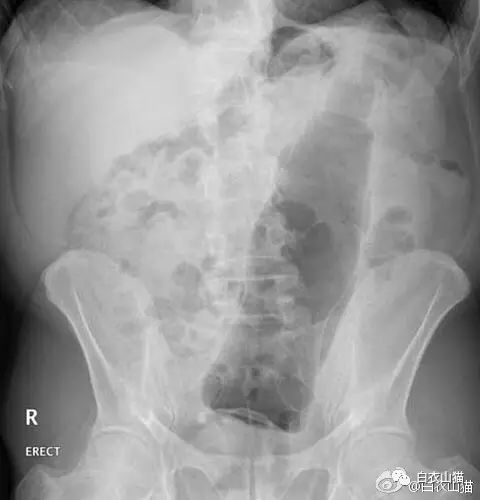

上面是近年医院里的一个病人,也是乙状结肠新鲜穿孔。医生给他开腹手术,从腹腔里取出来的5条泥鳅和一条黄鳝。

该病人提供的病史,是自己把活泥鳅和黄鳝生吞下去所导致。其实,医生一看泥鳅和黄鳝的颜色以及肠穿孔的部位,就知道怎么回事了。